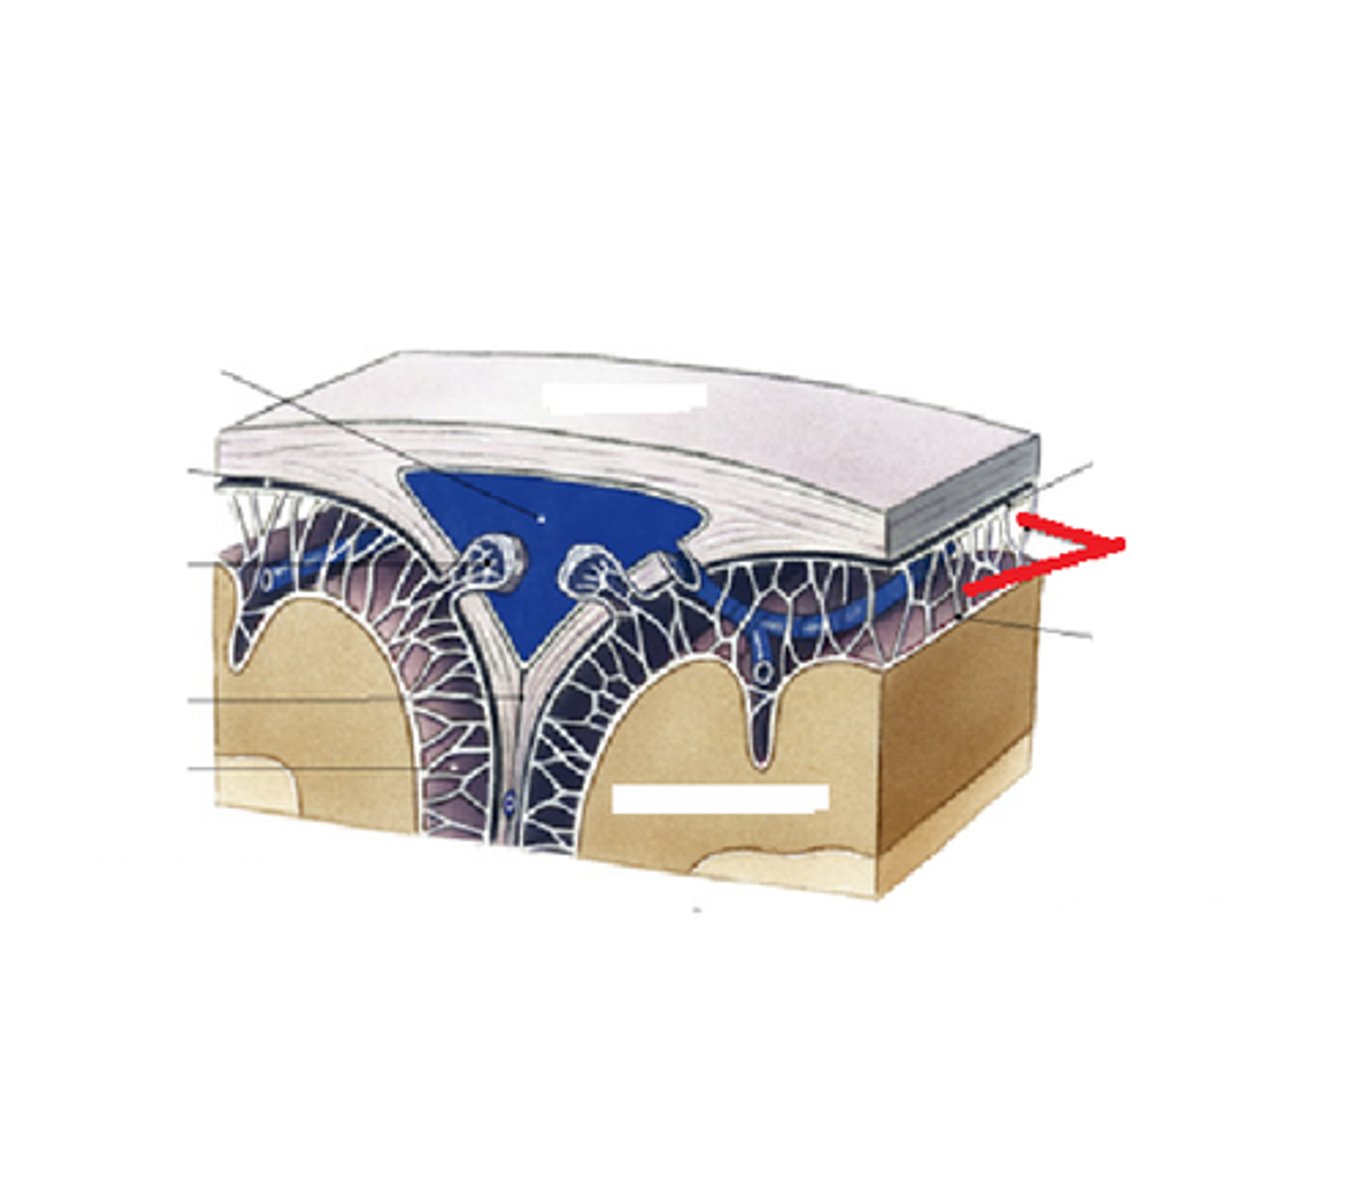

arachnoid

middle layer of meninges; weblike appearance that attaches it to deepest layer

arachnoid trabeculae

superior sagittal sinus

subdural space

space between dura mater and arachnoid mater

subarachnoid space

arachnoid mater

pia mater

the delicate innermost membrane enveloping the brain and spinal cord.

Cerebral Spinal Fluid (CSF)

clear, colourless fluid that circulates within the brain and spinal cord, serving several important functions in the CNS

Circulation of CSF

CSF from the lateral ventricles → interventricular foramina → third ventricle → cerebral aqueduct → fourth ventricle → subarachnoid space or central canal.